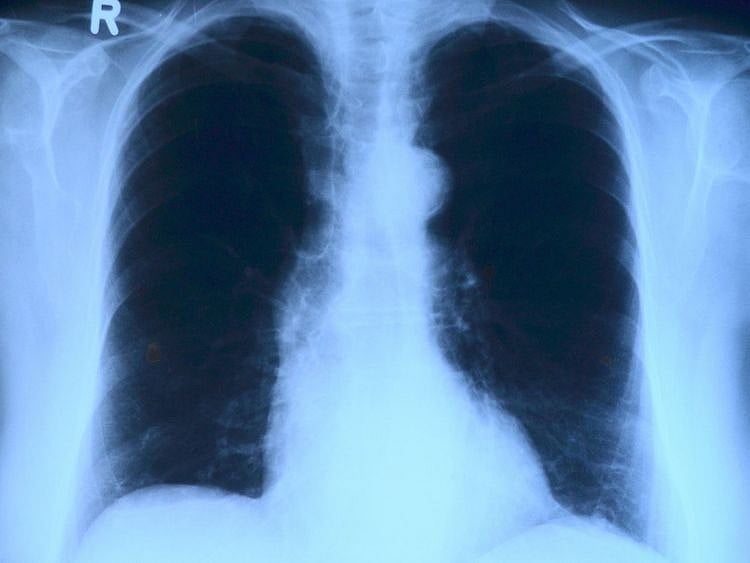

Canberra: Researchers have found that fatty tissues accumulate in the airway walls, particularly in people who are overweight or obese.

The study, published in the European Respiratory Journal, suggested that the fatty tissue alters the structure of people's airways and this could be one reason behind the increased risk of asthma.

The study showed that fatty tissue accumulates in the walls of the airways. The analysis revealed that the amount of fat present increases in line with increasing BMI.

"We've found that excess fat accumulates in the airway walls where it takes up space and seems to increase inflammation within the lungs," said the study's co-author Peter Noble.

"We think this is causing a thickening of the airways that limits the flow of air in and out of the lungs, and that could at least partly explain an increase in asthma symptoms," Noble said.